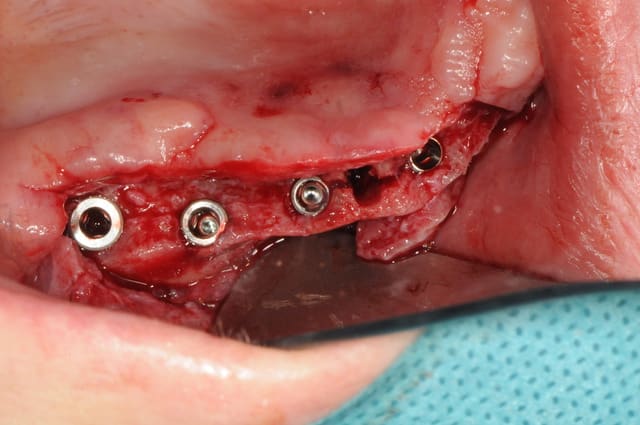

bon, ben mercredi c'était finalement sur 8 implants! mais ça devrait le faire quand même.

montage de tous les piliers coniques et vérification avec le guide chirurgical la position.

Dsc 6336 whbhaz - Eugenol

Dsc 6337 cdmte1 - Eugenol

Dsc 6338 kn2hio - Eugenol

Dsc 6339 rsxhzk - Eugenol